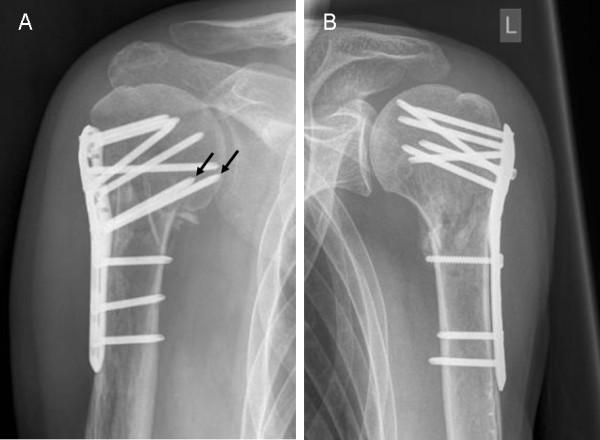

Follow-up was possible in 60 patients (C+ 6.7 ± 5.6 M/C- 5.0 ± 2.8 M). Humeral head necrosis occurred in 6 (C+, 15.4%) and 3 (C-, 14.3%) cases. Cut-out of the proximal screws was observed in 3 (C+, 7.7%) and 1 (C-, 4.8%) cases. In each group, 1 patient showed delayed union. Implant failure or lesions of the axillary nerve were not observed. In 44 patients, true AP and Neer views were available to measure the head-plate distance. There was a significant loss of reduction in group C- (2.56 ± 2.65 mm) compared to C+ (0.77 ± 1.44 mm; p = 0.01).

结果

60 例患者(C+组 6.7 ± 5.6 M/C-组 5.0 ± 2.8 M)获得随访。C+组有 6 例(15.4%)和 C-组有 3 例(14.3%)发生肱骨头坏死。C+组有 3 例(7.7%)和 C-组有 1 例(4.8%)发生近端螺钉切出。每组各有 1 例患者发生延迟愈合。未观察到内固定物失败或腋神经损伤。在 44 例患者中,可获得正位和 Neer 位 X 线片来测量头-板距离。C-组的复位丢失明显多于 C+组(2.56 ± 2.65 mm 比 0.77 ± 1.44 mm;p = 0.01)。

结论

在肱骨近端骨折的角稳定钢板固定术中,骺板螺钉的置入可提供内侧支撑,从而减少继发性复位丢失。但也未能显示并发症风险增加。